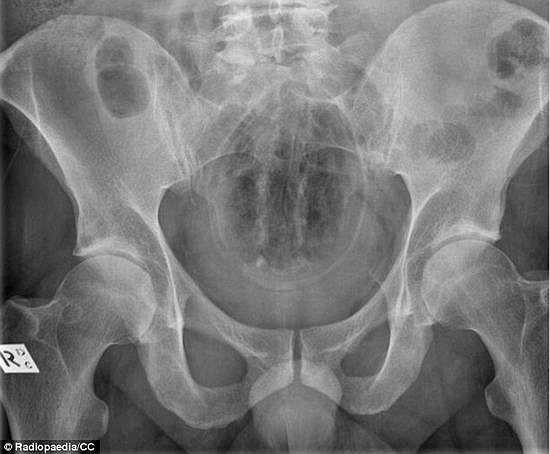

Một trường hợp tương tự là trái cam cũng không may lọt vào trực tràng.